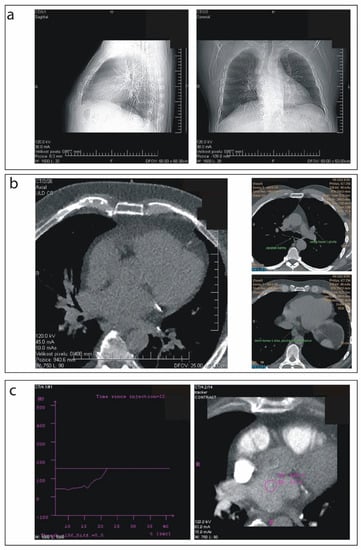

2.2. Scanning Procedure

2.4. 3D Left Atrium Model Segmentation and Image Quality Assessment

2.5. CT-EAM Integration and Procedural Usefulness